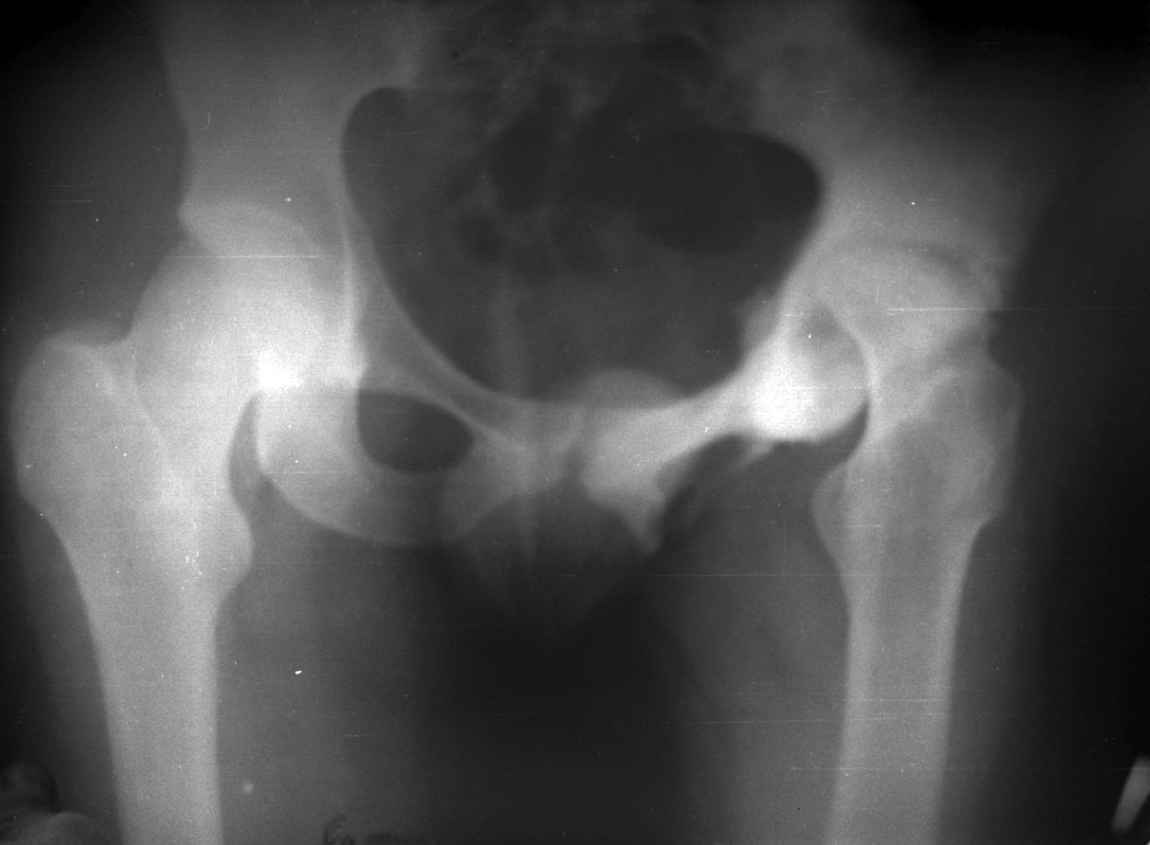

.........наверное не повезло. Но иногда это выход и очень хороший. М., 21 года спрыгнул в Армии с машины с исходом в гнойный коксит, свищевой формой в течении 1,5 лет. Операция проведена в 1988 году. результат хороший и сейчас и мы с пациентом хорошие приятели (Рентг-гр и фото прилагаю).